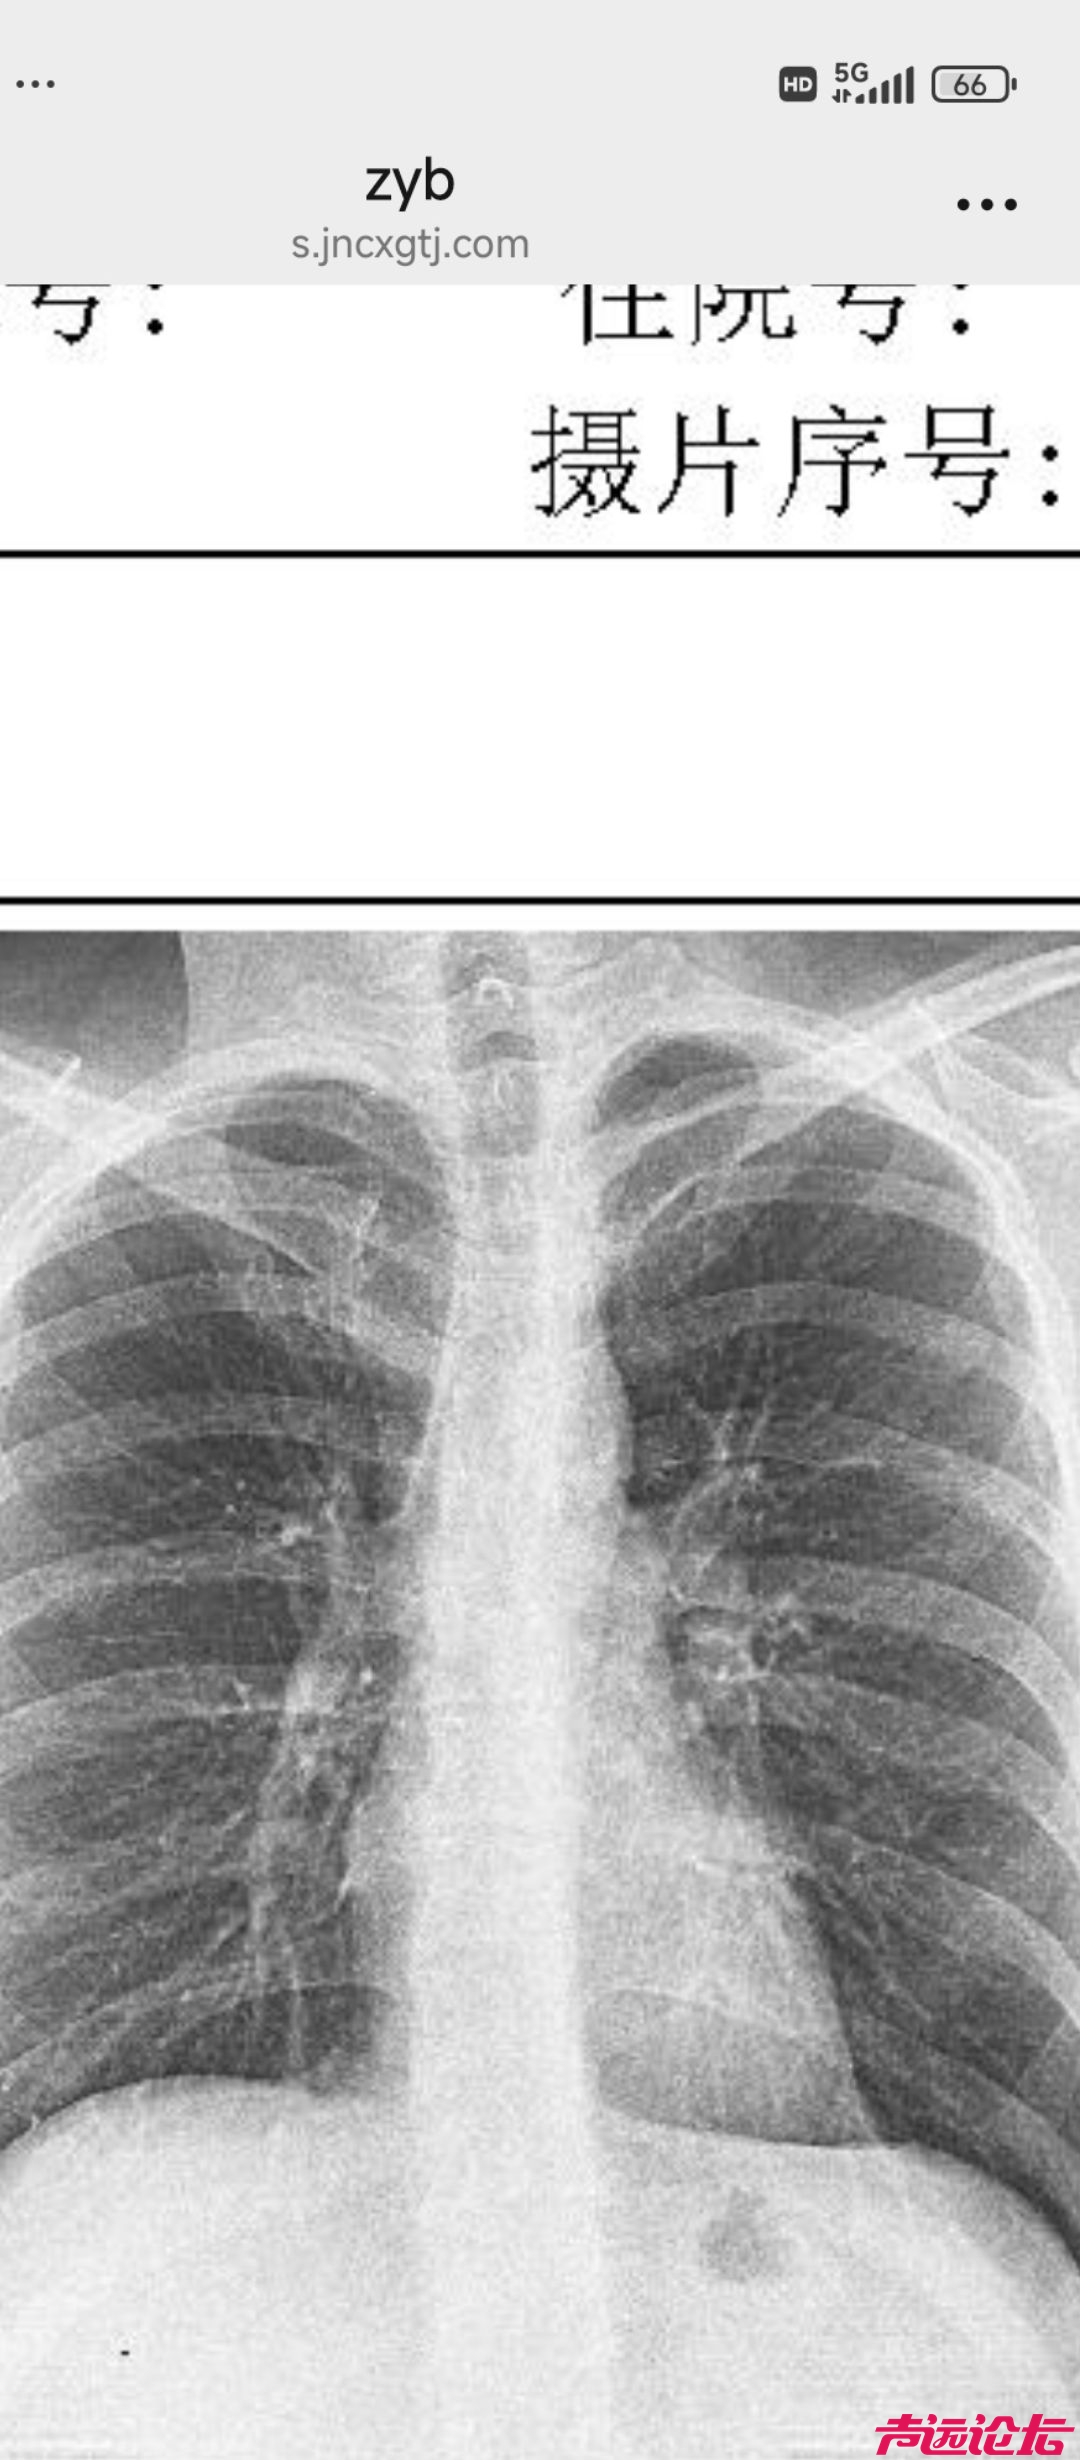

[济宁资讯] 脊柱侧弯影响大吗?

还能纠正过来吗?初中了是不是可以保守治疗?

能看出来,拍照片时一个肩膀高一个肩膀低。